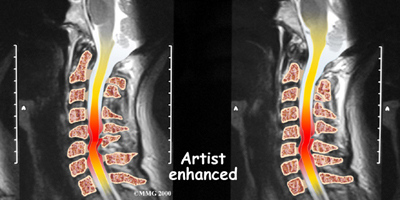

If more information is needed, your doctor may order an MRI. The MRI machine uses magnetic waves rather than x-rays to create pictures of the cervical spine in slices. MRIs show the cervical spine vertebrae, as well as the soft tissue structures, such as the discs, joints, and nerves. MRI scans are painless and don't require needles or dye. MRI scan has become the most common test to look at the cervical spine after x-rays have been taken.

DMX is a new fluoroscopic based x-ray system designed to objectively detect and document soft tissue/ligament injury most commonly associated with whiplash injuries of the spine. DMX evaluates biomechanical relationships and abnormal movements of the cervical spine. Specifically, DMX:

- Shows abnormal movement of vertebral bodies, facets, and other spinal elements

- Shows joint hypermobility, hypomobility, or restriction

- Shows normal or abnormal initiation of cervical motion

Example of DMX diagnostic video fluoroscopy.

DMX uses digital and optic technology now available. DMX is the latest generation of videofluoroscopy (VF) that uses low doses of radiation. The images have improved clarity and resolution over VF and are recorded digitally on CD or DVD disc. DMX digital images can be replayed and studied on standard computer systems. DMX images are simply x-ray images taken at 30 frames per second to form a multiple radiographic array or series that can be run as a movie file to display real time motion of the joints of the body.

DMX radiographic series can be paused at any location and the measurements and interpretation common to radiology can be applied to the still images. These images would be identical to plain film images if plain film radiography were performed at the same location at the same moment in motion. DMX acquires approximately 2700 images for the same amount of radiation as seven regular x-rays.